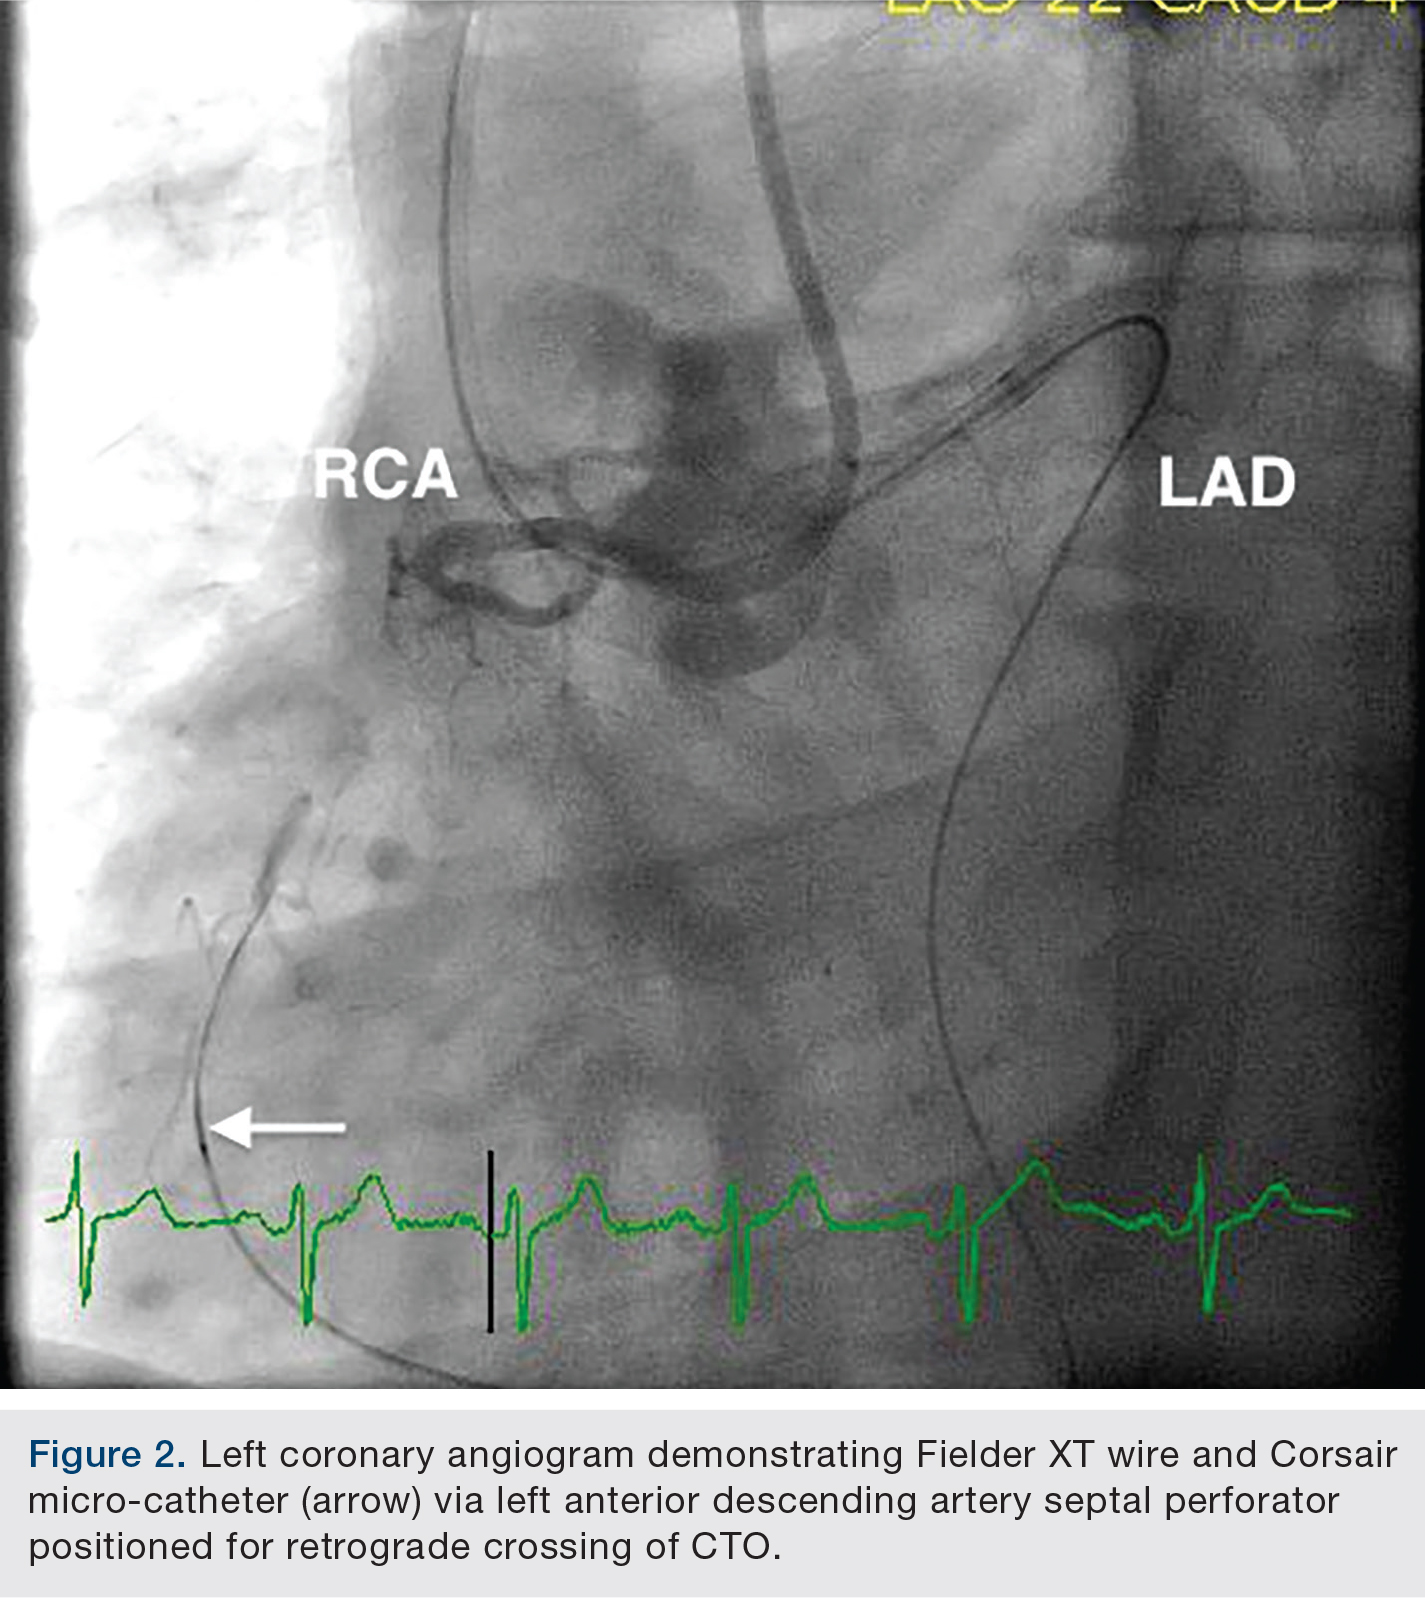

The patient underwent bilateral femoral artery access with 8 French sheath placement. An 8 French Extra Back Up Launcher 4.0 guide catheter (Medtronic) was positioned in the left coronary system and a 7 French Amplatz Left-1(AL-1) (Medtronic) positioned in the RCA ostium. The proximal RCA CTO cap was very ambiguous, with septal collaterals supplying the distal RCA (Figure 1). A retrograde approach via well-developed septal artery perforators was accessed with an Asahi Fielder XT wire (Abbott Vascular) and a 150cm Corsair micro-catheter (Asahi Intecc) (Figure 2).